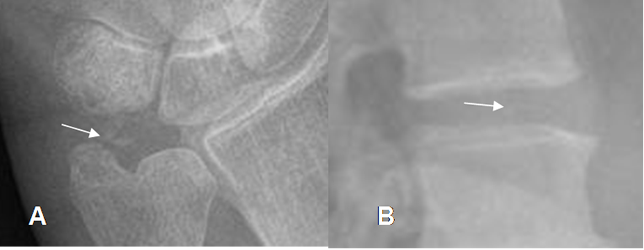

Fig 37. Artropatía por cristales.

A: Rx AP. Calcificación del fibrocartílago triangular.

B: Rx lateral. Calcificación del disco intervertebral.